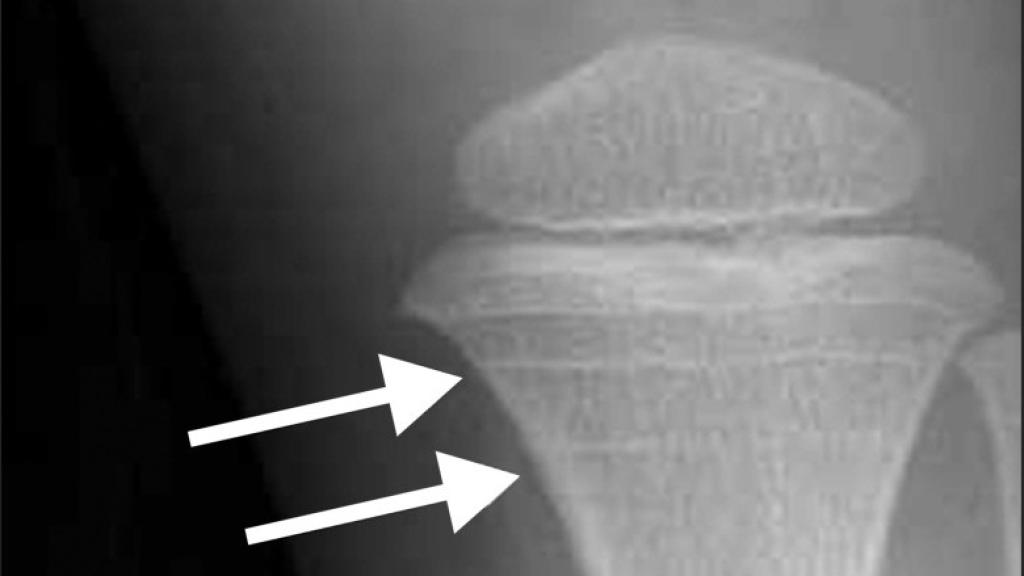

Las líneas de Harris son unas líneas, valga la redundancia, que se producen en los huesos largos cuando se da una interrupción temporal del crecimiento longitudinal del hueso, normalmente, a causa de una enfermedad. Un día, mientras trabajaba en el depósito de cadáveres, reparó en el caso que manejaba un forense, el de un niño de ocho años que se había suicidado. Su colega estaba buscando, a través de las radiografías, huellas de fracturas que pudieran indicar algún tipo de maltrato, aunque, por el momento, no había nada que indicase algo fuera de la normalidad. "Recuerdo que, sin que nadie me lo pidiera, dije 'qué interesante', al distinguir tres o cuatro líneas de Harris recientes", escribe Black.

Líneas de Harris publicadas en el trabajo 'Hallazgos incidentales en radiografías de rodilla en niños y adolescentes'.

Su apreciación fue lo que comenzó un interrogatorio a los progenitores, en principio, en busca de alguna enfermedad que pudiera haber pasado el niño, hasta que el padre terminó desmoronándose. Al parecer, cuando era pequeño, su padre había abusado de él y sospechaba que ahora estuviera haciendo lo mismo con su hijo. La policía interrogó al abuelo, que finalmente terminó confesando. Las líneas de Harris del chico eran la respuesta al miedo y a la tensión que sentía ante la inminente visita de su abuelo.